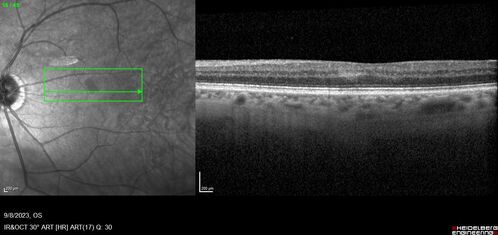

Paracentral acute middle maculopathy - isolated

83 year old man New spot in the vision yesterday left eye.

Medical Hx: Pure Hypercholesterolemia

Systemic Meds: Crestor.

VA OD: Dcc20/20

VA OS: Dcc20/20

IOP: TP: OD:19 OS:10